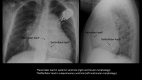

Transvenous interventional implantation of CRT-D in a critically ill Mustard patient waiting for heart transplant

Cardiac resynchronization therapy may stabilize patients with severe heart failure awaiting heart transplant. Transvenous interventional implantation aided by intracardiac echocardiography is feasible in patients with adult congenital heart disease.